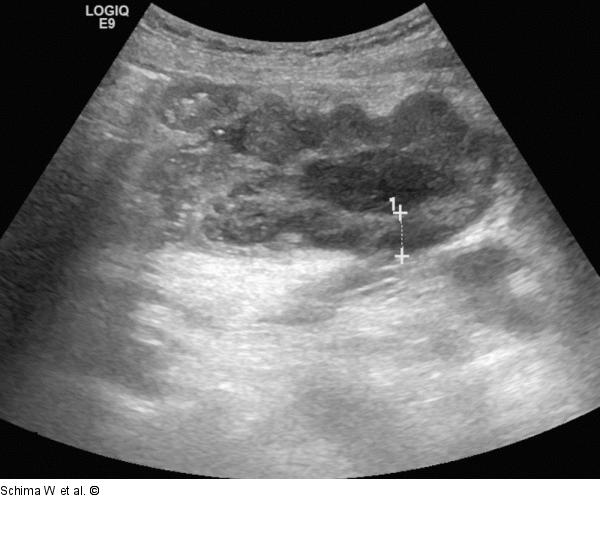

Abbildung 1: Tumor Die Sonographie zeigt im Unterbauch einen zentral liquid-nekrotisch imponierenden Tumor. Eine genaue Zuordnung zu einem Darmsegment ist nicht möglich. |

Die Sonographie zeigt im Unterbauch einen zentral liquid-nekrotisch imponierenden Tumor. Eine genaue Zuordnung zu einem Darmsegment ist nicht möglich. |